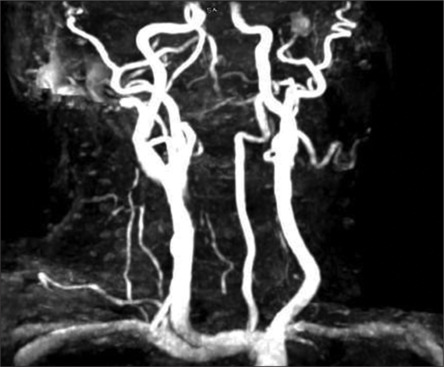

Carotid endarterectomy (CEA) is an established method of stroke prevention in patients with severe carotid artery stenosis, especially in those with symptomatic disease. Complications of CEA include perioperative stroke, cranial nerve palsy, hemorrhage, and vascular dissection. We present an unusual case of a 66-year-old man who presented for elective right CEA for symptomatic 70% right internal carotid artery (ICA) stenosis due to ulcerated plaque. Following surgery, the patient developed fluctuating neurological deficits consistent with involvement of the right middle cerebral artery territory. Imaging revealed possible mild clamp-induced ICA dissection limited to the ICA in the neck. Despite initial successful anticoagulation management in the neurointensive care unit, the patient returned 2 days later with stroke symptoms, necessitating urgent endovascular intervention. Neurovascular interventions involved aspiration thrombectomy and multiple stenting extending distally into intracranial ICA, which successfully restored cerebral arterial perfusion and normal neurological function. This case highlights the first reported instance of extensive intracranial ICA dissection managed with full-length stenting. This article offers an effective endovascular procedure for preventing a devastating stroke from a complication of a procedure that was performed to prevent it.